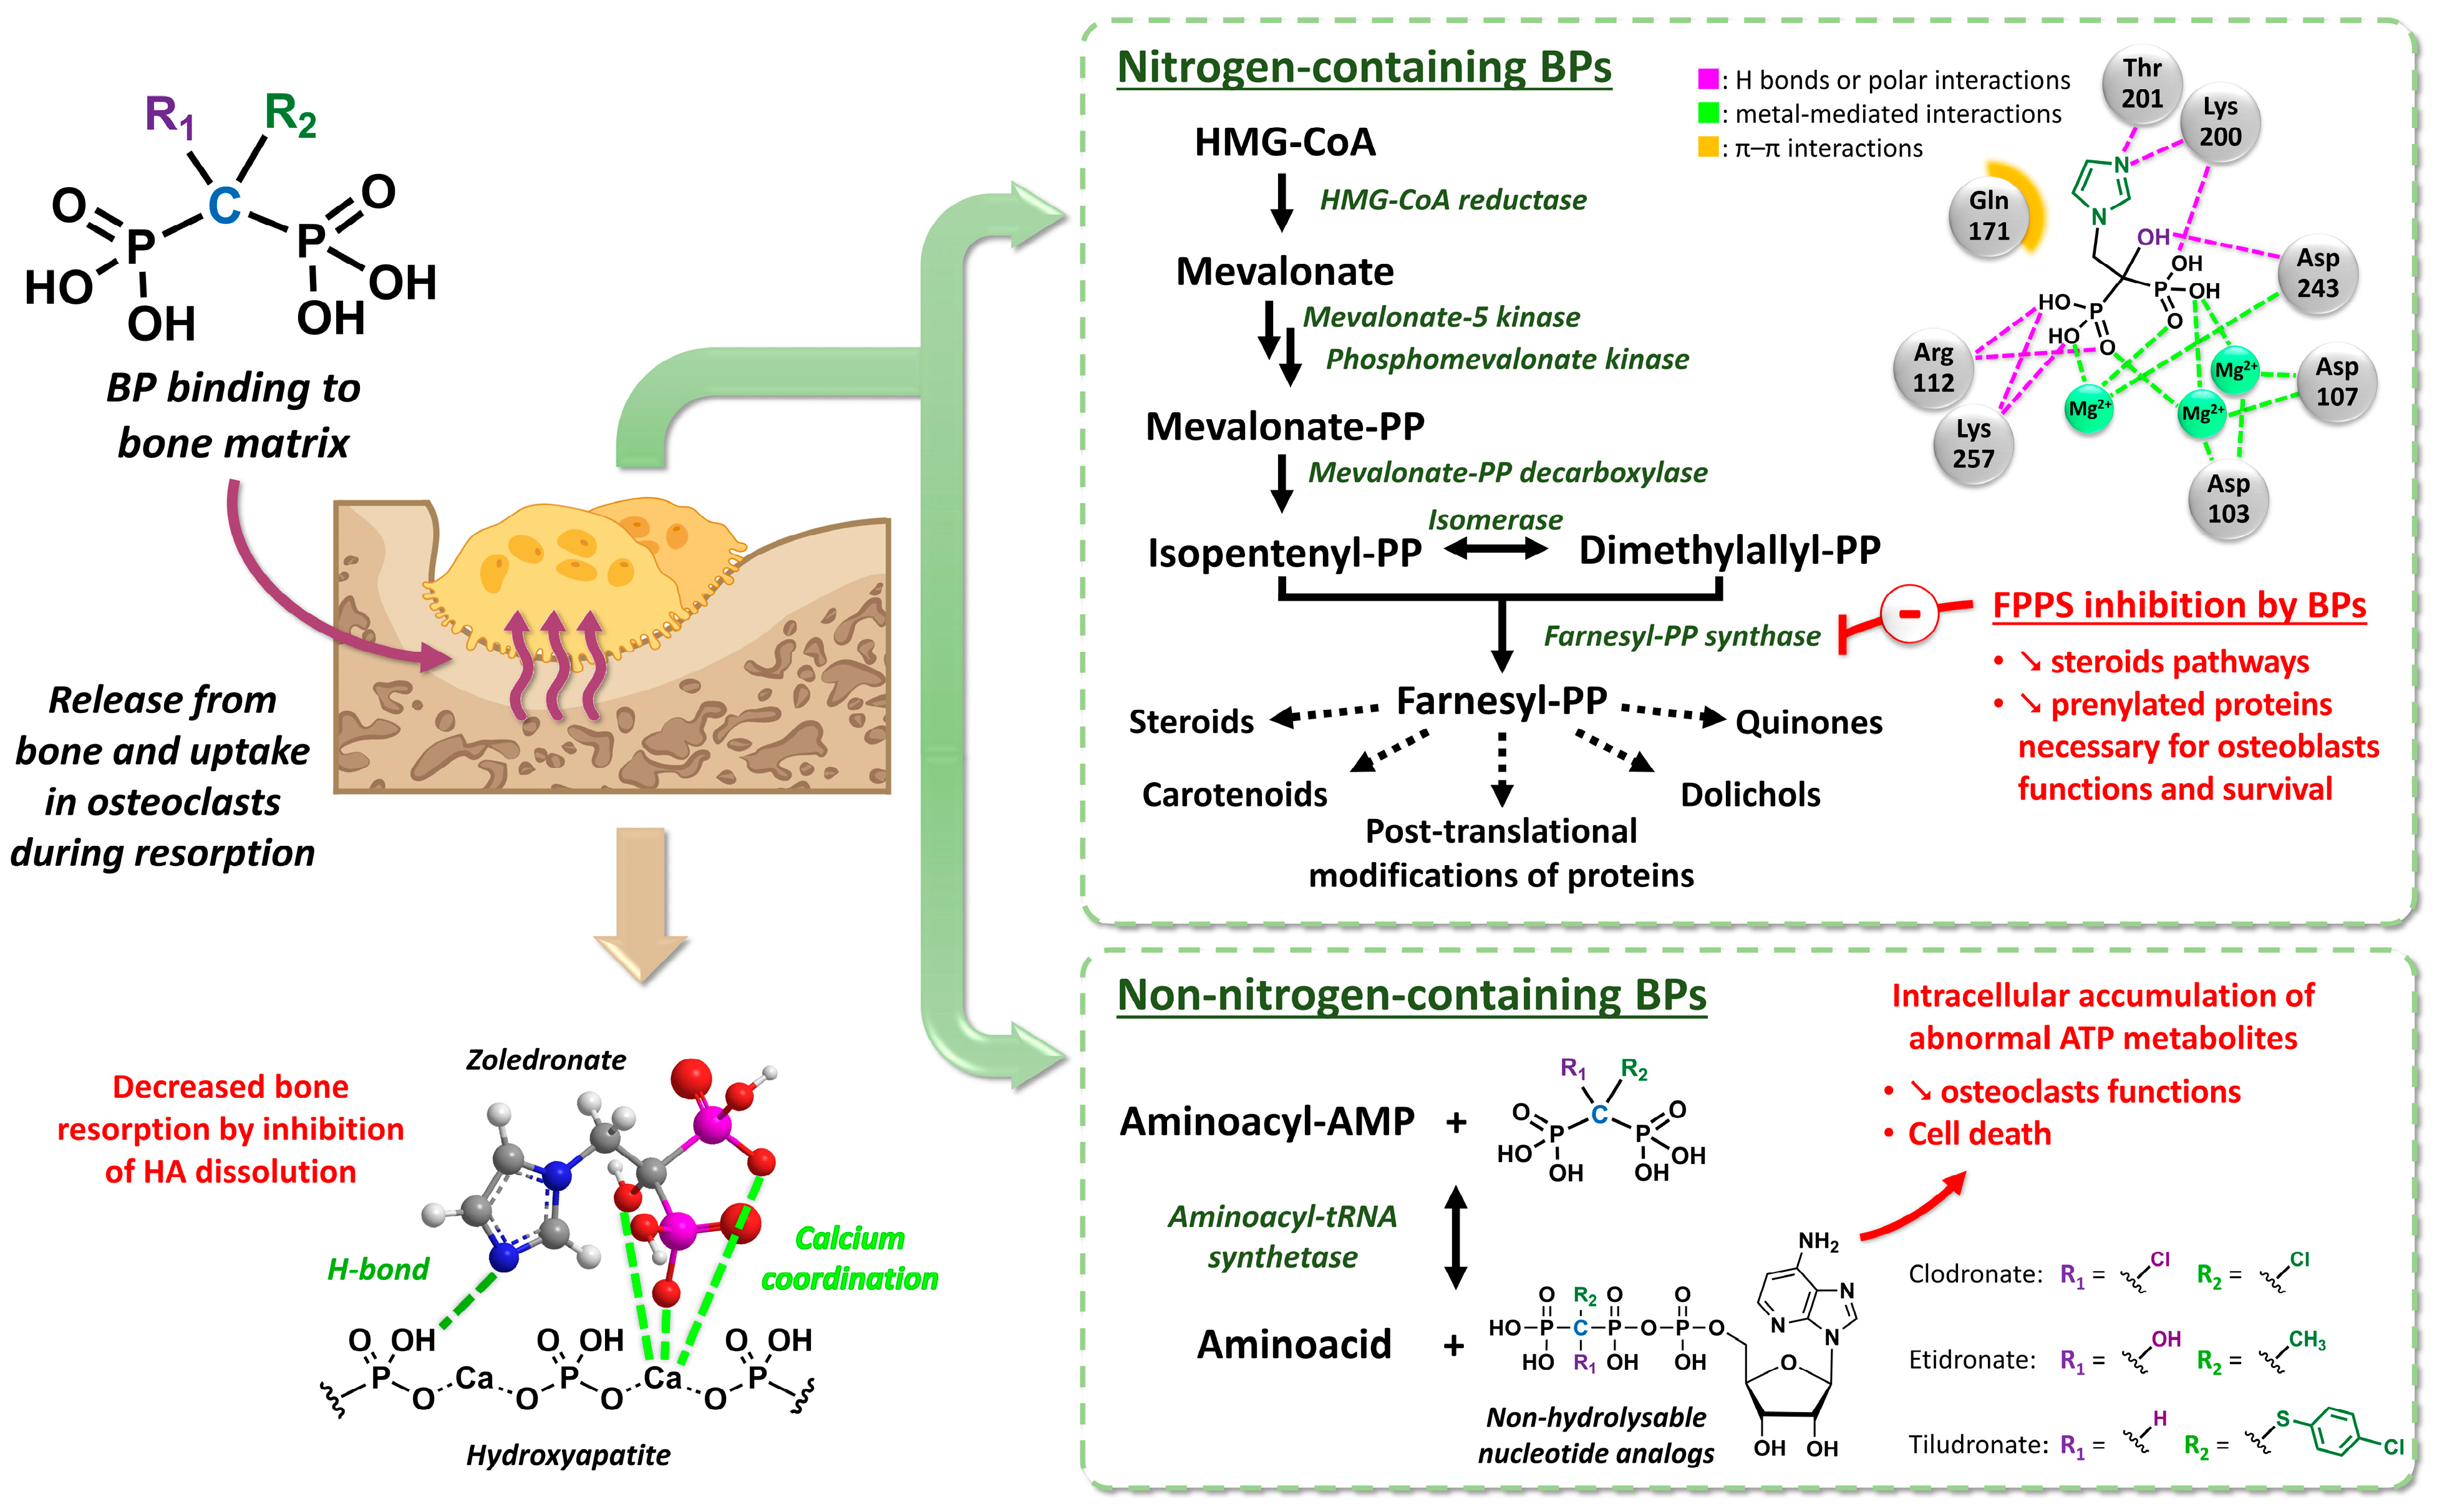

2.1. Development and Pharmacology Basics of Bisphosphonates

2.2. Bone Metastases Molecular Targeting and Early Bisphosphonate-Based Radiopharmaceuticals

- Specific bone targeting based on the electronic properties of a free radioactive atom: two isotopes of the same atom do not differ in their electronic structure and therefore have identical chemical properties, which allows skeletal targeting by the isotopes of atoms with natural affinities for bone. This applies to [18F]fluoride ions, which replace hydroxide anions in hydroxyapatite crystals to form fluoroapatite in the bone mineral [82]. The [18F]NaF PET imaging agent tends to be more accurate than bone scintigraphy for the detection of skeletal metastatic lesions in several types of cancer [83,84,85,86]. In therapy, [32P]orthophosphate (t1/2 = 14.3 days; Eβ-max = 1.71 MeV) is also incorporated into hydroxyapatite crystals [87] and was historically used to treat painful osteoblastic metastases [88]. This treatment showed moderate efficacy with the disappearance of pain symptoms in almost half of patients [89] but caused common bone marrow toxicity, especially in patients with renal impairment. Likewise, the chemical elements in the same group/column of the periodic table of elements are characterized by the same number of valence electrons, and therefore, by usually comparable chemical reactivity. Part of the same group as calcium, 89Sr (t1/2 = 50.5 days; Eβ-max = 1.49 MeV) is an alkaline earth metal that accumulates in lesions with high osteoblastic activity and has been used under its dichloride salt form in the palliative treatment of pain associated with bone metastases [90], especially in prostate cancer. The initial clinical trials with this radiopharmaceutical in monotherapy showed modest effects on pain control in bone metastases associated with substantial bone marrow toxicity [91,92,93], while its use in patients treated with doxorubicin [94] or docetaxel [95] tended to improve both the symptoms associated with bone metastases and survival. Similarly, alpha-emitting radionuclide 223Ra (t1/2 = 11.4 days; Eα = 5.0 to 7.5 MeV [95.3%]; Eβ-max = 1.37 MeV and 1.42 MeV [3.6%]) showed an overall survival benefit in patients with metastatic prostate cancer, with a significant 9-month delay in bone-related events when associated with a bone-protecting agent (e.g., denosumab) [96]. To date, radium-223 dichloride (Xofigo®, Bayer, Leverkusen, Germany) is the only FDA- and EMA-approved targeted alpha therapy available.

- Specific targeting based on a vector molecule with bone tropism: in scintigraphic imaging, medronate (MDP) [97] and oxidronate (HMDP) [98,99] were among the first bisphosphonates to be used as bone scintigraphy imaging vectors on humans after the pioneering application of [99mTc]Tc-etidronate [100,101,102,103] (Figure 5). These two compounds are characterized by their simple chemical structures, which do not contain dedicated chelation sites. Although their formulation in single-vial cold kits for radiopharmaceutical preparation makes 99mTc radiolabeling simple and ensures high radiochemical purity levels, [99mTc]Tc-MDP and [99mTc]Tc-HMDP complexes do not form a single defined chemical entity but are rather structured into a mixture of monomers, oxo-bridged dimers and oligomeric clusters of varying sizes, featuring diverse technetium-oxo core arrangements, oxidation states and ligand coordination numbers [104] with a composition that varies according to pH, technetium concentration and oxygen amount [105]. Lastly, the phosphonate groups of MDP and HMDP (as well as the hydroxyl group of HMDP) serve both as coordination sites with 99mTc and as recognition sites for the bone mineral matrix. Consequently, the bone affinity of the corresponding 99mTc complexes is intrinsically reduced [106]. Even so, these radiopharmaceuticals remain reference bone scintigraphy agents, either in oncology for cancer staging [107,108] and therapeutic response evaluation [109,110,111] or in benign bone disorders such as Paget disease [112,113] or primary hyperparathyroidism [114,115]. Interestingly, 99mTc-radiolabeled butedronate (2,3-dicarboxypropane-1,1-diphosphonate, DPD, Figure 5) [116] is another SPECT imaging agent with the same indications as [99mTc]Tc-MDP and [99mTc]Tc-HMDP but also has a particular role in the detection of cardiac amyloidosis [117,118,119]. Concerning therapy, a bisphosphonate-related derivative with an ethylenediamine tetraphosphonate structure (EDTMP, also named lexidronam) radiolabeled with 153Sm (t1/2 = 1.9 days; Eβ-max = 0.81 MeV) has also been used since the late 1980s [120,121] for the relief of pain resulting from bone metastases; two clinical trials demonstrated its efficacy in this indication versus the placebo and its improved toxicity profile compared to 89Sr and 32P [122,123]. Notably, etidronate was also selected for radionuclide therapy applications after radiolabeling with beta minus-emitting rhenium isotopes, either 186Re or 188Re [9,10,11,12,13,14,15,16,17,18,19,20,21], but with rather limited clinical use.